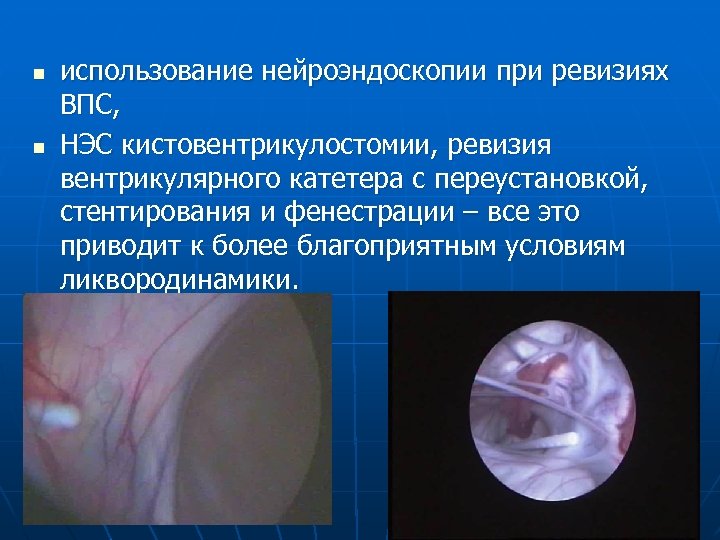

Профилактика: n n Установка вентрикулярного катетера в передний рог бокового желудочка Подбор клапана подходящего давления Имплантация катетера в «чистый ликвор» При ревизии вентрикулярного катетера - использование НЭС, коагуляция внутри катетера

n n использование нейроэндоскопии при ревизиях ВПС, НЭС кистовентрикулостомии, ревизия вентрикулярного катетера с переустановкой, стентирования и фенестрации – все это приводит к более благоприятным условиям ликвородинамики.